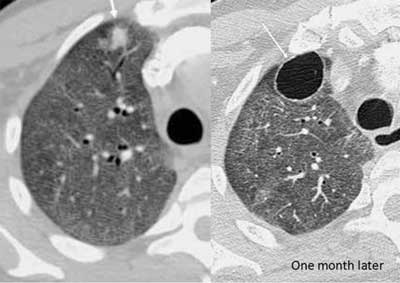

肺空洞ct图片,空洞型肺结核ct图片

肺空洞性病变和囊性病变的ct诊断

肺空洞愈合的ct图片

肺结核空洞ct图片解释